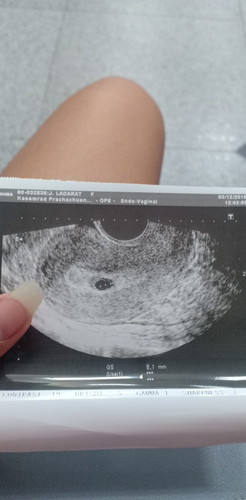

ท้อง 2 เดือนแล้วค่ะ มีเลือดออกมาแต่หมอฉีดยากันแท้งให้ค่ะ แต่ทำไม 2 เดือนเป็นจุดเล็กๆแบบนี้หรอค่ะ น้องยังอยู่กับเราใช่ไหมค่ะ

เป็นไปได้หลายเหตุผลนะคะ อาจจะไข่ตกช้า ยังไงรอซาวด์อีกรอบค่ะ